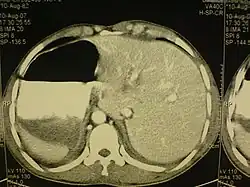

El Situs inversus es una extraña malformación genética que puede afectar a varios órganos y tiene un carácter genético. Consiste en una alineación errónea de los órganos dentro del cuerpo, colocándolos del lado opuesto (imagen de espejo).

Generalmente va asociado a otras malformaciones, tales como poliesplenia, Síndrome de Kartagener, etc. Suele representar un serio riesgo para la vida pues en la mayoría de los casos va acompañado de malformaciones cardíacas (véase Dextrocardia). También representa un problema en cuanto a la presentación de síntomas de algunas enfermedades, por ejemplo la apendicitis en un paciente con situs inversus presenta el dolor en el lado izquierdo, al igual que en el caso de un infarto al corazón en el cual el dolor característico se ubica en el brazo derecho.